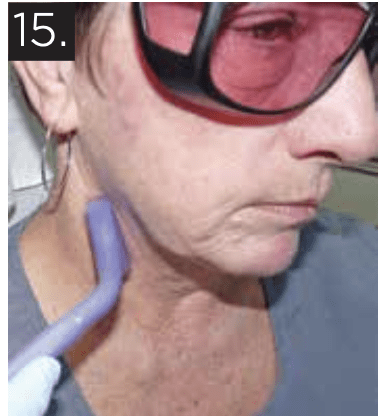

Dr. Burchman advocates for dentists to adopt photobiomodulation (PBM) therapy, highlighting its benefits in pain relief and tissue healing. He shares his mission to promote PBM as an alternative to opioids in dental practices.

This is the original citing of the post by Dr. Gerry Ross: Laser therapy is not a foreign concept in most dental practices, as many practitioners include soft tissue surgical lasers in their arsenal of […]